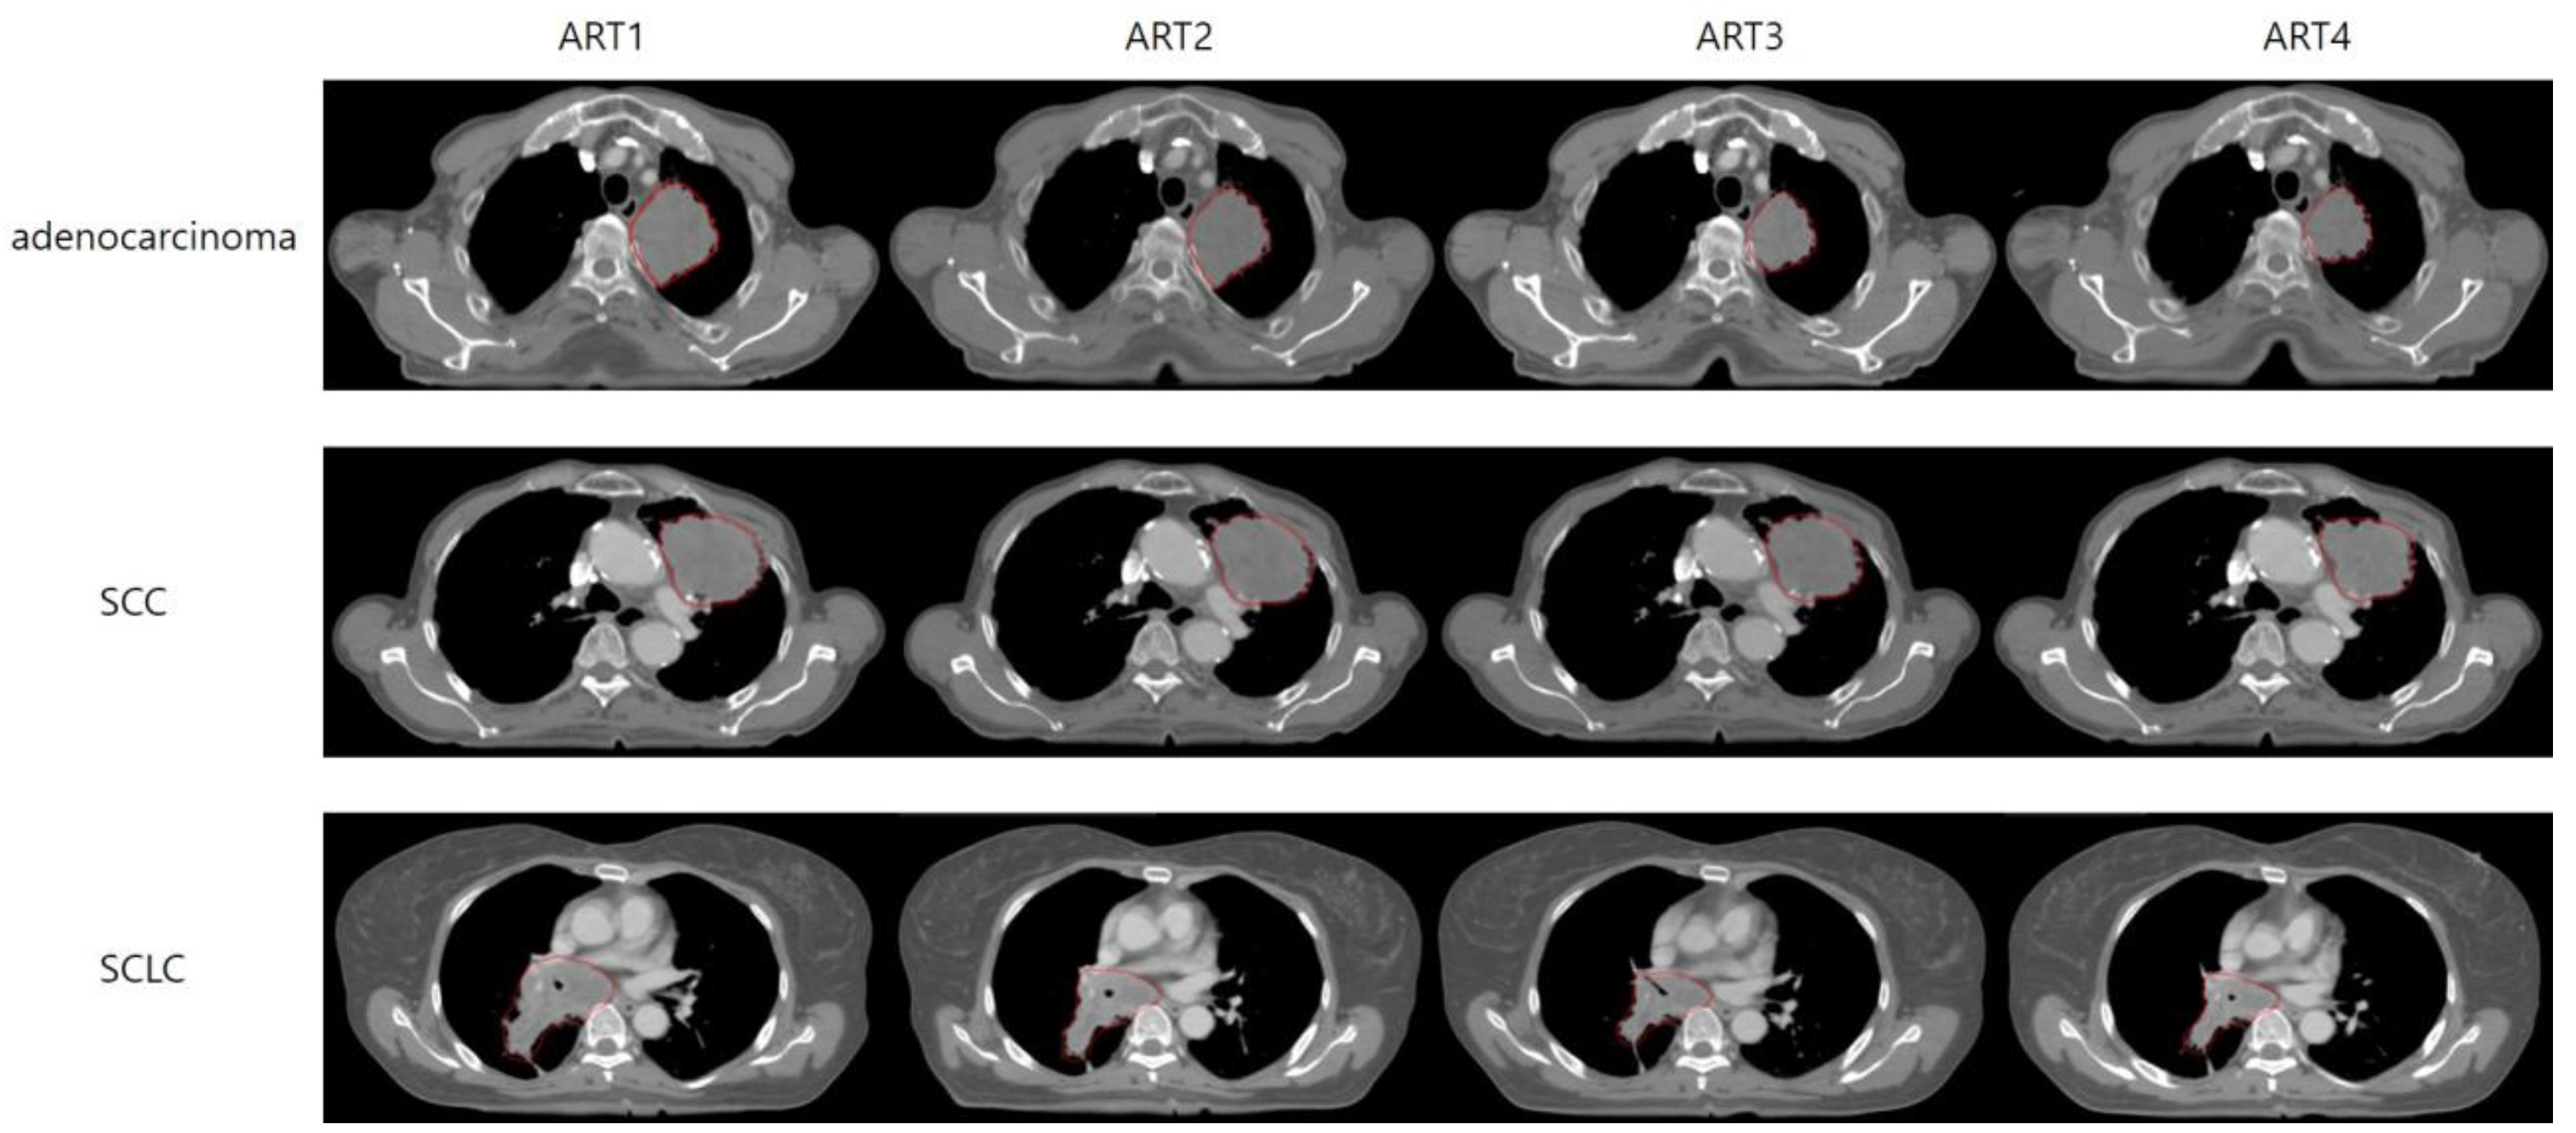

Figure 2.

Demonstration of GTV reduction over ART stages in patients with adenocarcinoma, SCC, and SCLC. The figure displays a selection of CT images from one patient each for the adenocarcinoma, SCC, and SCLC groups. In each set of images, the gross tumor volume (GTV) at the same anatomical section is presented from the initial plan to ART4. SCC, squamous cell carcinoma; SCLC, small-cell lung cancer; ART, adaptive radiotherapy.